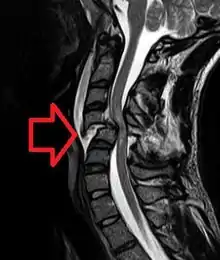

| Cervical spine MRI of a patient with SCI: C4 fracture and dislocation, spinal cord compression | |